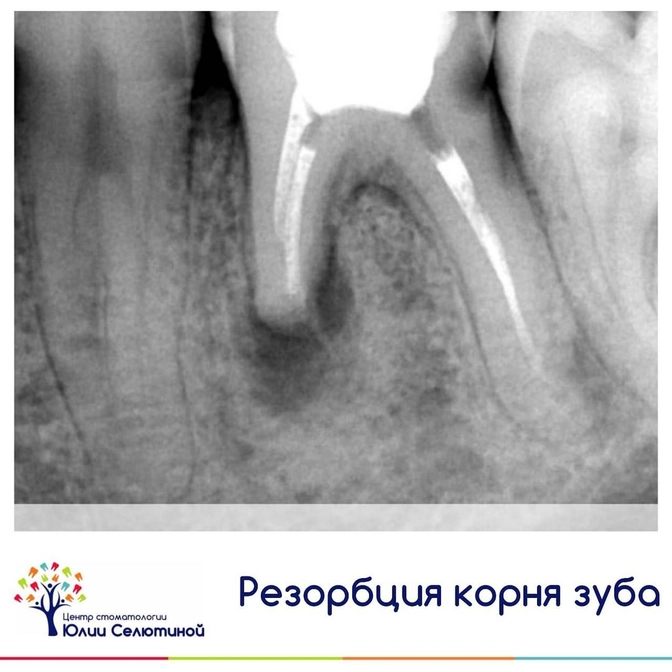

✔️Резорбция (или рассасывание) корня - это процесс убыли корней зуба и околокорневых тканей (костной, периодонта, цемента корня, дентина, пульпы).

1. Внутреннюю - очень часто идет бессимптомно.

Возникает при повреждении пульпы зуба (сосудисто-нервного пучка), тем самым идет перерождение этих тканей в гранулематозную, и грануляция постепенно ведет к рассасыванию тканей зуба.

2. Наружную - бывает цервикальная, поверхностная, заместительная, воспалительная.

Она характеризуется разрушением корня снаружи.

Диагностируется с помощью снимка либо на КТ.

Внутреннюю резорбцию часто находят внезапно на снимке, и пациент даже не подозревает, что корень уже начал рассасываться.